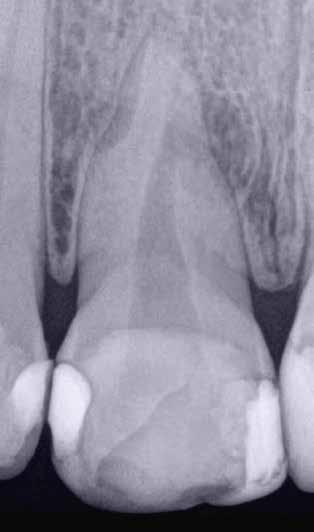

1. a–f ábrák: A cingulumon keresztül gömbfúróval kialakított hozzáférés a trepanációs kavitás labiális irányba történő túlzott mértékű kiterjesztését eredményezheti, és ez lényegesen növelheti a perforáció esélyét (a). A guttapercha átsejlik a lágyrészek alatt (b). Klinikailag igazolt perforáció (c). A preoperatív sagittális irányú CBCT-szeleten jól látható a labiális perforáció (d). Labiális irányú perforáció (fekete nyíl; e). A tényleges gyökércsatorna (piros nyíl; f).

5. a–l. ábrák: Az incisális élen keresztül kialakított hozzáférés lehetővé teszi a pericervikális dentin megőrzését. Kalcifikáció esetén CBCT-felvétel készítése hasznosnak bizonyulhat a hozzáférési nyílás tervezése során (a–d) . Minden fog koronai helyreállítása a gyökértömés elkészítésével egyidejűleg történt. A négyéves (e–h) és a kétéves (i–l) kontrollok alkalmával készített röntgenfelvételeken teljes gyógyulás látható. Mindkét fog tünetmentes és funkcióképes volt. (Dr. Viraj Vora esetei)

kialakítása során fennáll a fog labiális irányú perforációjának veszélye, mivel ilyenkor a foganyag elvételét labiális irányú fúrótartással kezdjük. Nemrégiben újragondolták a

hozzáférési nyílás kialakítási protokollt, amelyet már ko

rábban, két endodonciai közleményben közzétettek. Ezekben a frontfogak hozzáférési nyílásainak kialakítását inci

sálisabb megközelítéssel javasolták. 21,22 Az új ajánlásban azt javasolják, hogy a frontfogakban történő hozzáférési nyílás kialakítását a cingulumtól távolabb, inkább az incizális él közelében kezdjük meg 19. Ez lehetővé teszi a lehető legtöbb pericervikális dentin megőrzését és kizárólag a legszükségesebb mennyiségű dentin kerül eltávolításra. Emellett ez a kialakítás a cingulumon keresztül történő hozzáféréshez képest egyenesebb hozzáférést biztosít a labiális és a linguális, vagy palatinális csatornákhoz, valamint lehetővé teszi a csatornák hatékonyabb tisztítását. 21 A fogak kopása esetén a hozzáférést az incisális „felszín” közepén alakítjuk ki (3. a-b ábrák) . A frontfogak kezelése során a megfelelő fúró kiválasztása is kiemelkedően fontos szereppel bír. A korábban ajánlott gömbfúrók használata ma már kifejezetten kontraindikáltnak számít. A gömbfúrók használatakor jellemzően egy fordított tölcsér alakú üreg kerül kialakításra. Ezekben az esetekben az üreg egyre szélesebb lesz, ahogy egyre mélyebbre hatolunk a fúrónkkal (2. a-b ábrák) 23 A gömbfúrók helyett olyan fúrók használata javasolt, amellyel elkerülhető lehet a trepanációs kavitás túlzott mértékű kiterjesztése, és amely segítségével a hozzáférési nyílás legszűkebb részét a pericer -

vikális dentin területének megfelelően tudjuk kialakítani (4. ábra) 19 Ezáltal képesek vagyunk a lehető legnagyobb volumenű pericervikális dentinállomány (PCD) megőr -

zésére. Ez azért fontos, mert a frontfogak funkcionális megterhelése során – a PCD-nek megfelelően elhelyezkedő területben – jelentős stressz ébred (5. a–l ábrák) 24 Szükség esetén egy CBCT-felvételt is készíthetünk. A 3D-s adatok jelentős mértékben segíthetik a klinikus munkáját a gyökércsatorna koronális vetületének vizualizálásában, és ennek alapján az egyenes vonalú hozzáférés biztosításához szükséges belépési pont meghatározásában (5.